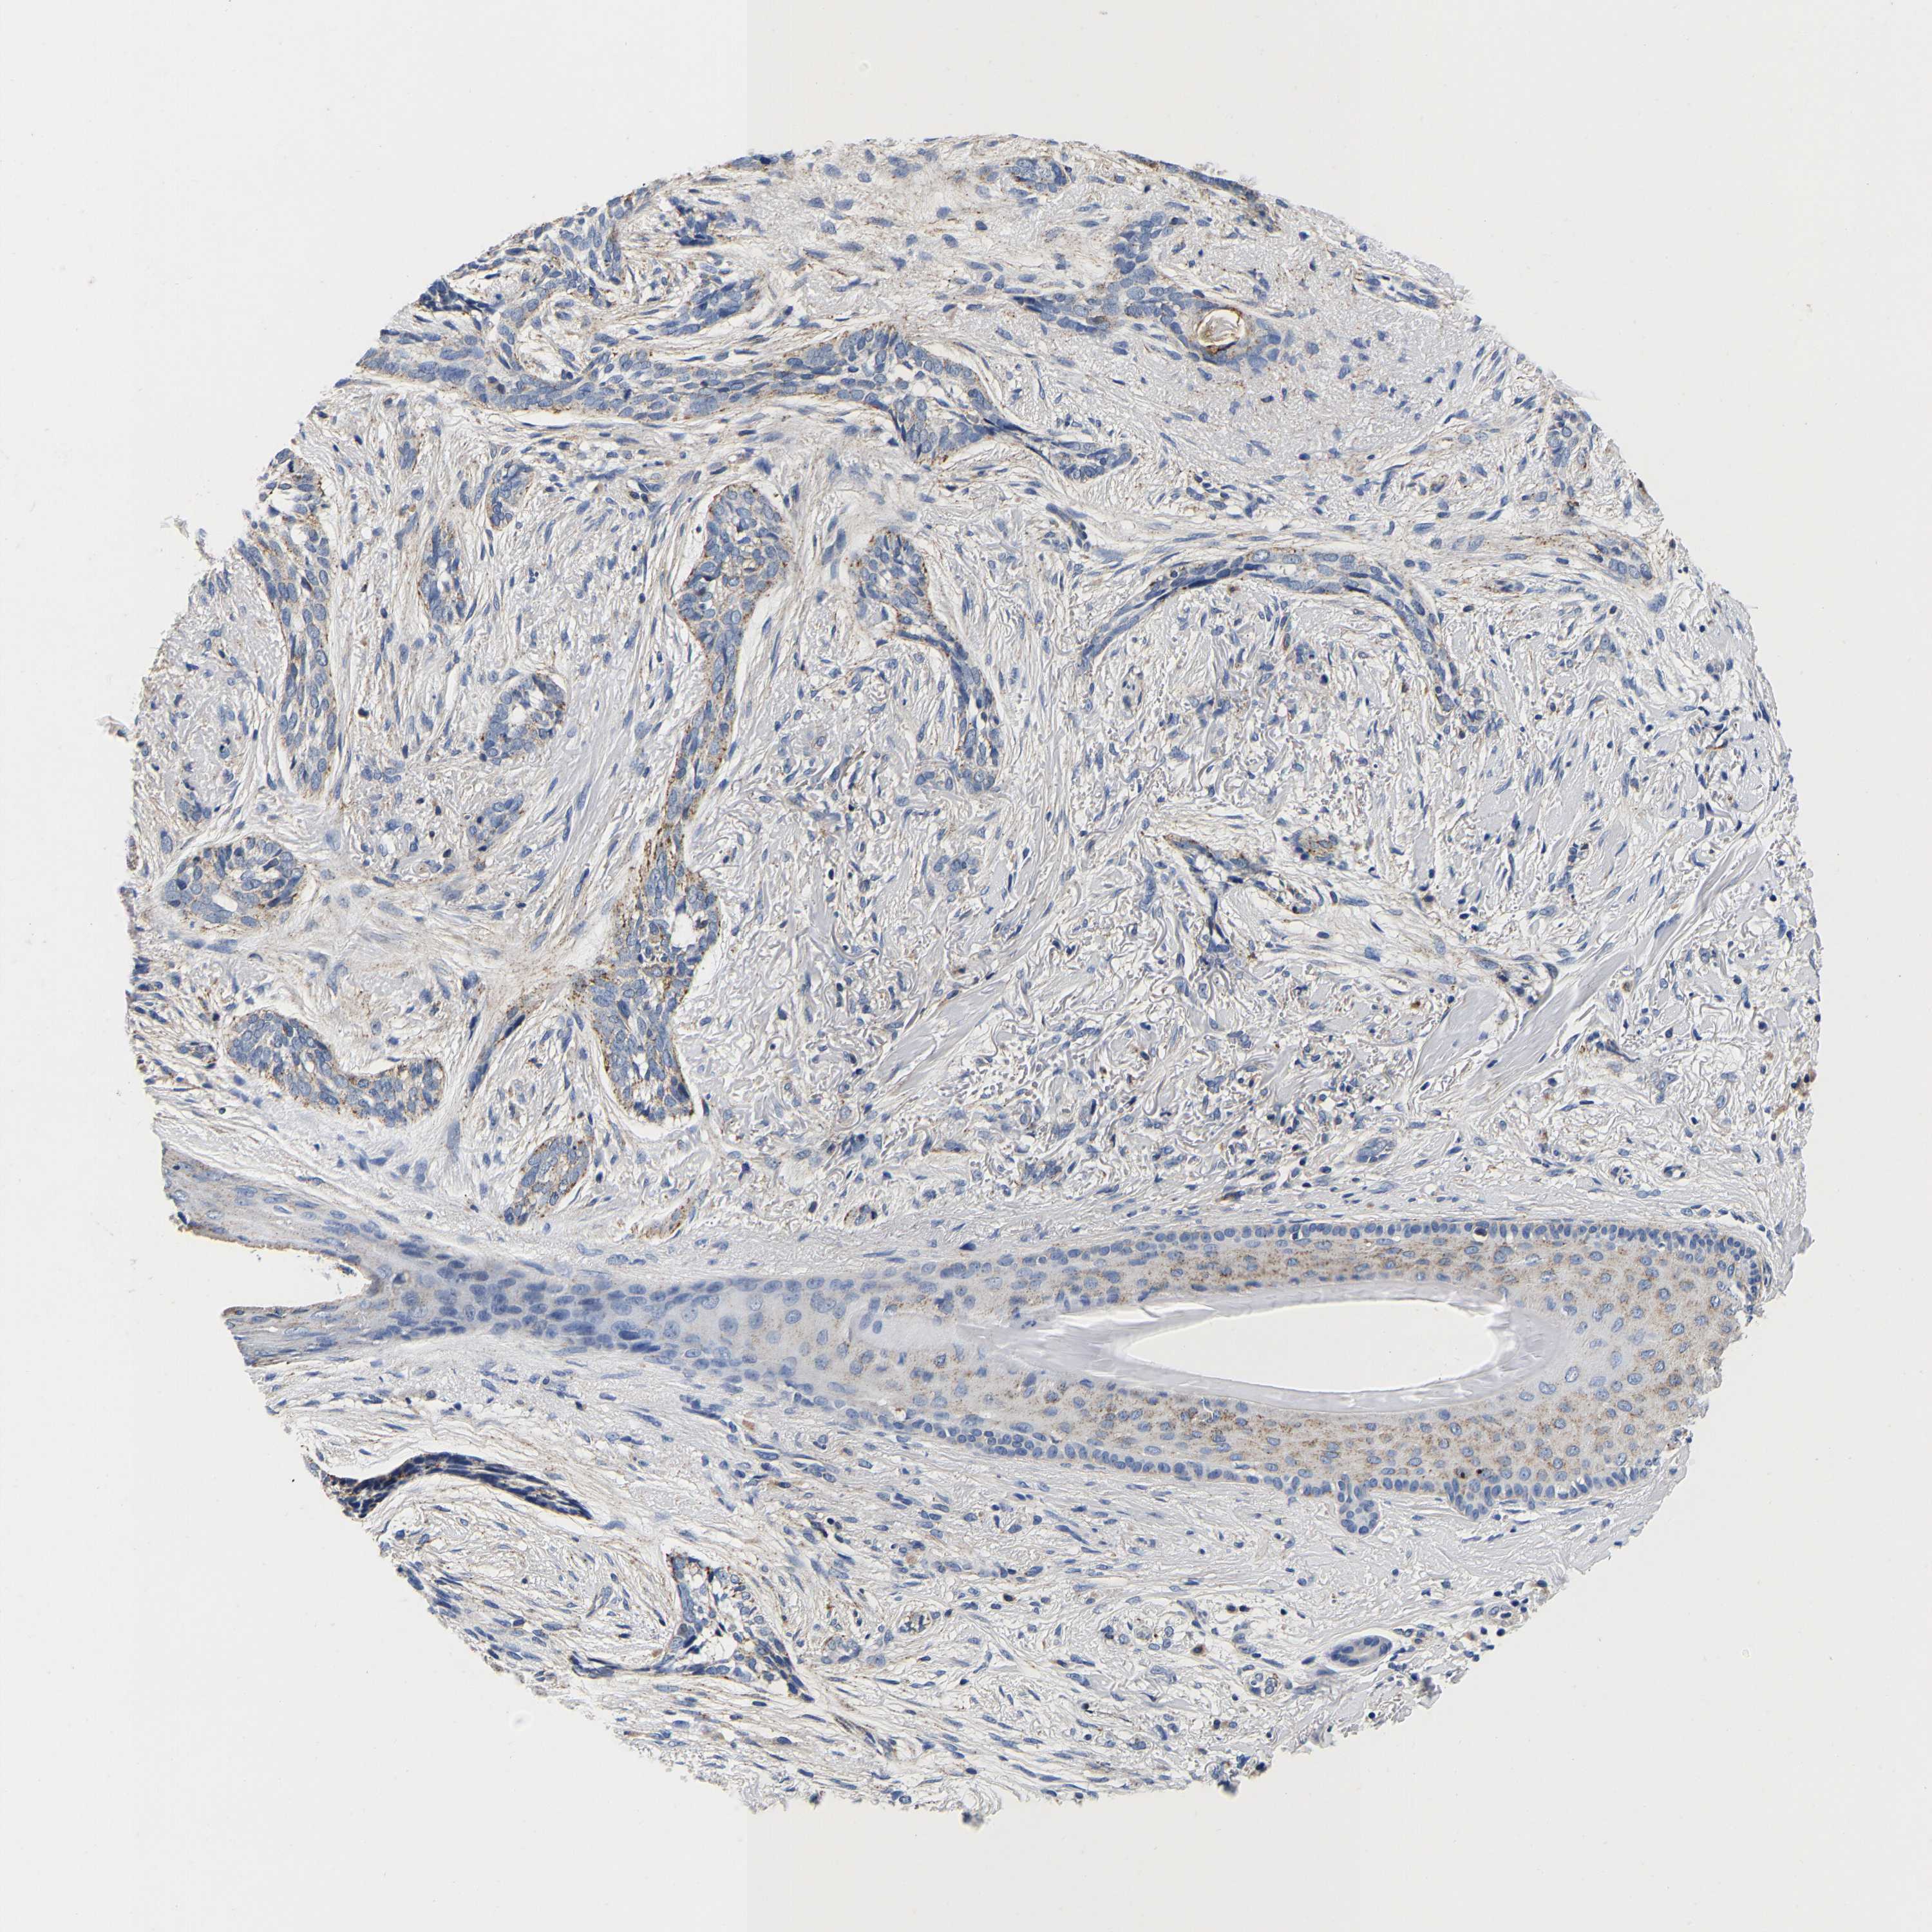

SKIN CANCER - Protein expressioni

A mouse-over function shows sample information and annotation data. Click on an image to view it in a full screen mode. Samples can be filtered based on level of antibody staining by selecting one or several of the following categories: high, medium, low and not detected. The assay and annotation is described here.

Antibody stainingi

Antibody staining in the annotated cell types in the current human tissue is reported as not detected, low, medium, or high, based on conventional immunohistochemistry profiling in selected tissues. This score is based on the combination of the staining intensity and fraction of stained cells.

Each image is clickable and will lead to virtual microscopy that enables deeper exploration of all samples and also displays staining intensity scores, fraction scores and subcellular localization as well as patient and tissue information for each sample.

Antibody HPA008763

Staining

Not detected

Negative

None

Squamous cell carcinoma, NOS